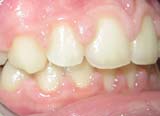

κλινική εικόνα ουλίτιδας περιοδοντίτιδα σε γυναίκα 22 ετών ακτινογραφική εικόνα περιοδοντίτιδας

Η περιοδοντική νόσος προσβάλλει τους ιστούς που στηρίζουν τα δόντια στη γνάθο και εμφανίζεται σε παιδιά, εφήβους και ενήλικες. Το ποσοστό των ατόμων που πάσχουν αυξάνεται με την ηλικία. Έτσι ένα μεγάλο μέρος του πληθυσμού έχει ήδη τη νόσο και ένα ακόμα μεγαλύτερο θα νοσήσει τα επόμενα χρόνια. Η περιοδοντική νόσος εκδηλώνεται ως ουλίτιδα, ως περιοδοντίτιδα ή ως μια τοπική διαφοροποίηση στα ούλα (π.χ. υπερπλασία).

- Ουλίτιδα είναι η φλεγμονή μόνο των ούλων, αποτελεί την αρχική μορφή της περιοδοντικής νόσου και αν δεν θεραπευτεί έγκαιρα μεταπίπτει σε περιοδοντίτιδα.

- Περιοδοντίτιδα είναι η εξάπλωση της φλεγμονής κάτω από τα ούλα που προσβάλλει τους ιστούς που συγκρατούν τα δόντια, με αποτέλεσμα τα δόντια να χάνουν τη στήριξή τους, να αποκτούν κινητικότητα και πολλές φορές να καταλήγουν σε εξαγωγή. Η περιοδοντίτιδα αποτελεί την κύρια αιτία απώλειας δοντιών στους ενήλικες.